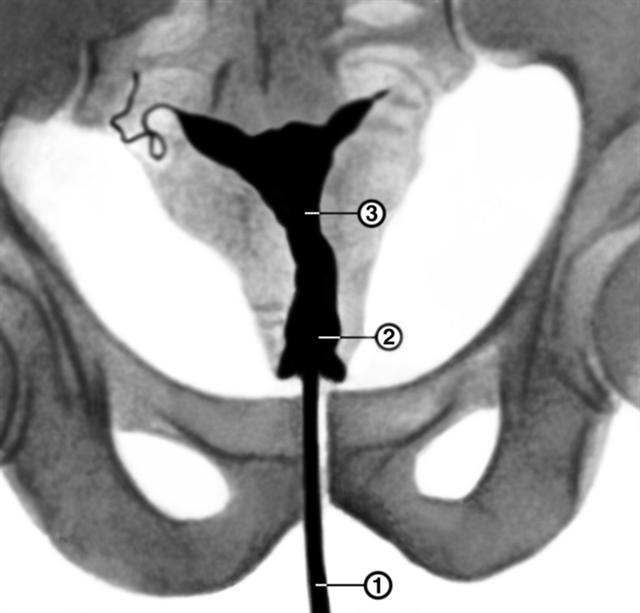

Рис. 1б). Гистерограмма при истмико-цервикальной недостаточности: 1 — перешеек матки, 2 — канал шейки матки, 3 — катетер, через который введено рентгеноконтрастное вещество; видно значительное расширение перешейка и канала шейки матки.